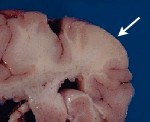

Морфология поражений нервной системы сводится к образованию в веществе и оболочках мозга туберов, кист, субэпендимальных узлов, нейрофибром, кальцификатов, участков глиоза, атрофии или демиелинизации; наличию врожденных аномалий питающих мозг сосудов (аневризм, АВМ, ангиом). Клинически наиболее часто наблюдается судорожный синдром, который может иметь различное течение и большую вариабельность пароксизмов.